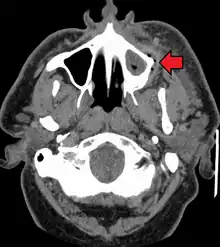

If left untreated, a severe tooth abscess may become large enough to perforate bone and extend into the soft tissue eventually becoming osteomyelitis and cellulitis respectively. From there it follows the path of least resistance and may spread either internally or externally. The path of the infection is influenced by such things as the location of the infected tooth and the thickness of the bone, muscle and fascia attachments.

External drainage may begin as a boil which bursts allowing pus drainage from the abscess, intraorally (usually through the gum) or extraorally. Chronic drainage will allow an epithelial lining to form in this communication to form a pus draining canal (fistula).[4] Sometimes this type of drainage will immediately relieve some of the painful symptoms associated with the pressure.

Internal drainage is of more concern as growing infection makes space within the tissues surrounding the infection. Severe complications requiring immediate hospitalization include Ludwig's angina, which is a combination of growing infection and cellulitis which closes the airway space causing suffocation in extreme cases. Also infection can spread down the tissue spaces to the mediastinum which has significant consequences on the vital organs such as the heart. Another complication, usually from upper teeth, is a risk of sepsis traveling through pathways to which it can possibly lead to endocarditis, brain abscess (extremely rare), or meningitis (also rare).